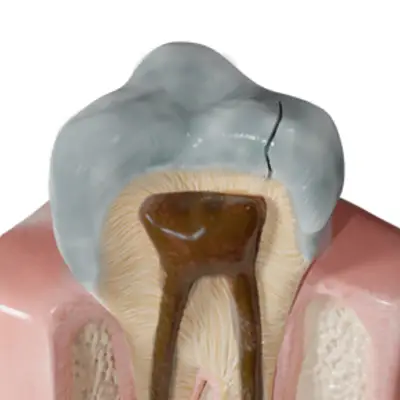

A root canal treatment is the dental procedure necessary to remove a dead pulp from within a tooth, allowing you to keep the hard structures of your tooth after the soft tissue is gone. During a root canal treatment, your dentist “opens” the tooth so that he or she can remove the dead or infected nerves and blood vessels from the hollow internal chamber of the tooth (which extends down into each root in a “canal” shape). The dentist then cleans and sterilizes each canal of the teeth and seals the chamber with a biocompatible filling material.

No, it will not. The change in your tooth’s color occurred when pigmented molecules embedded into the hard tooth structure. This darkened structure is not routinely drilled away during a root canal treatment because it is otherwise healthy and strong.

For teeth that suffered substantial loss of hard tooth structure (due to decay or fracture), the tooth will require full coverage with a dental crown. Your dentist can therefore match the covering crown to your natural teeth around the affected tooth.